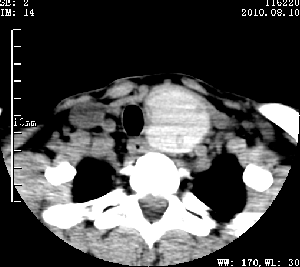

标题: CT28317:病人近几天无意间发现颈部肿块。 [打印本页]

标题: CT28317:病人近几天无意间发现颈部肿块。

甲状腺左叶局限性结节性甲状腺肿可能。建议增强扫描。

病变边界清楚,周围间隙清晰,甲状腺左叶(甲状旁腺?)肿大,右叶甲状腺腺瘤。

病变边界清楚,周围间隙清晰,左叶甲状腺肿大,右叶甲状腺小腺瘤。